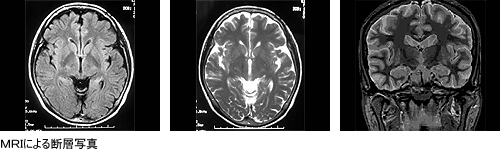

◆MRA検査

MRI 装置を使用した血管撮影(MR Angiography)のことで、造影剤や薬を使わずに脳や頚の血管を写す検査です。脳動脈瘤や血管の細い部分などを発見できます。検査の受け方はMRI と同じで、仰向けに横になって頂いて検査をします。